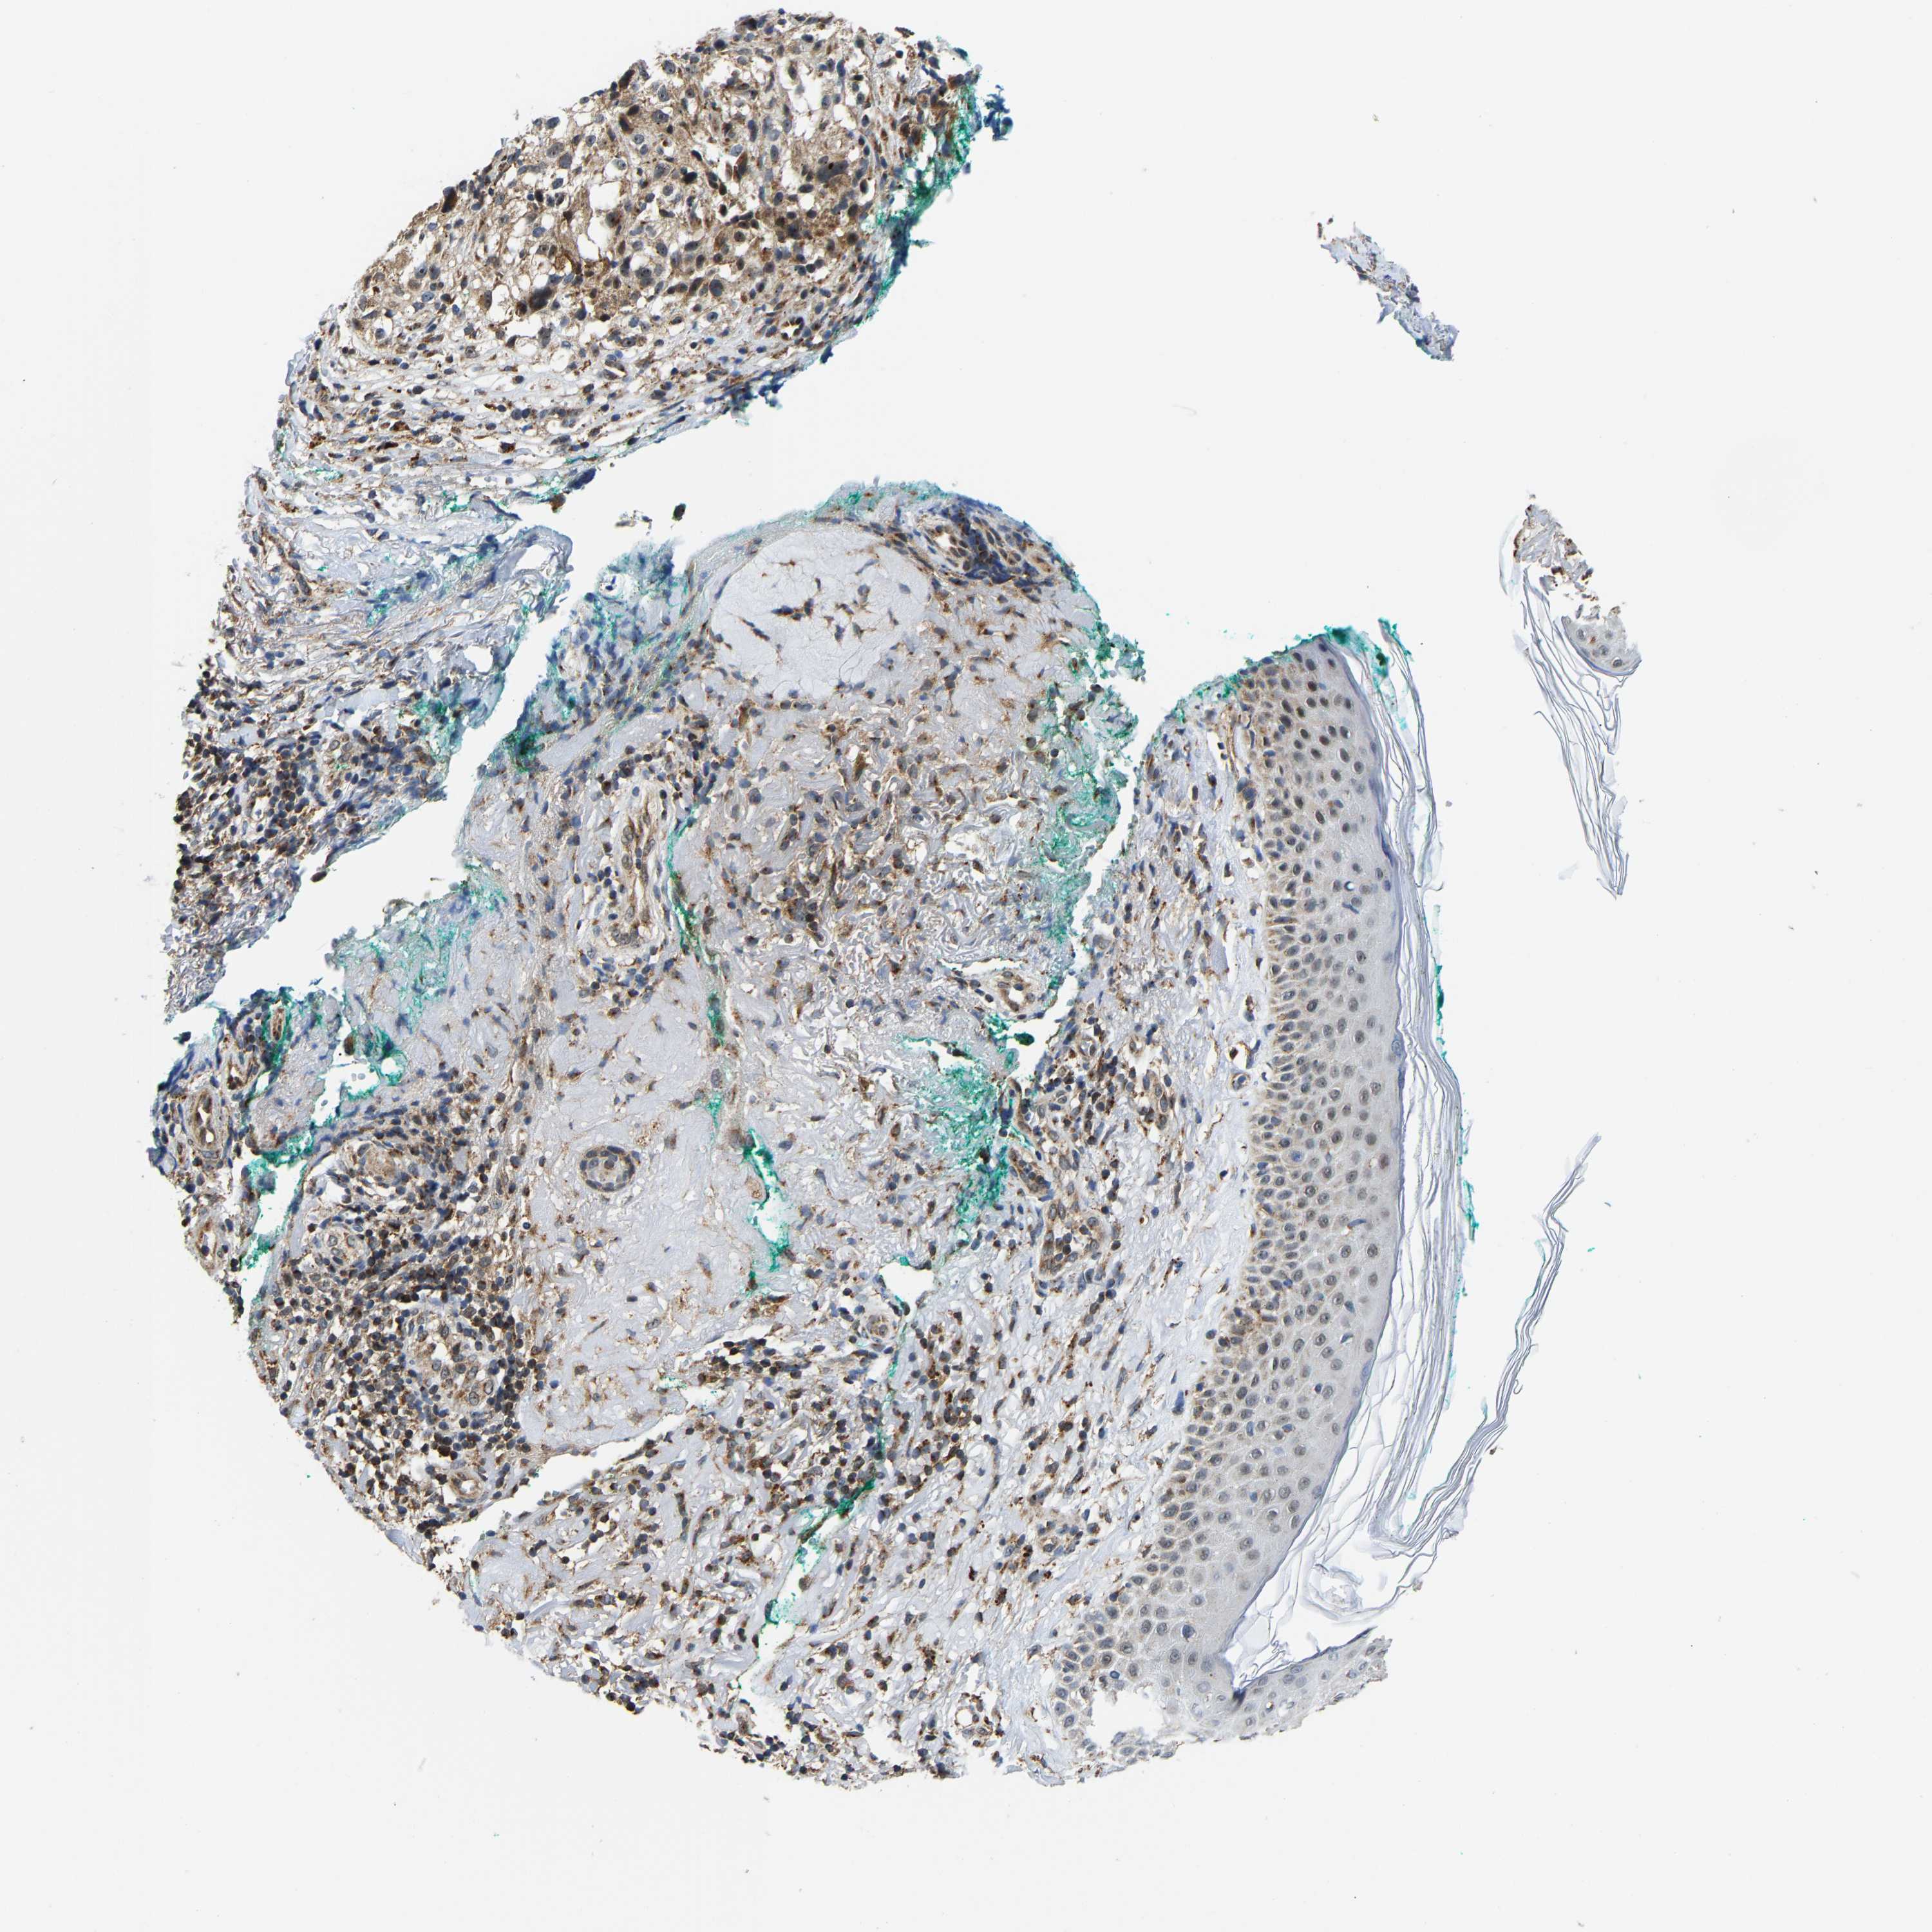

MELANOMA - Protein expressioni

A mouse-over function shows sample information and annotation data. Click on an image to view it in a full screen mode. Samples can be filtered based on level of antibody staining by selecting one or several of the following categories: high, medium, low and not detected. The assay and annotation is described here.

Note that samples used for immunohistochemistry by the Human Protein Atlas do not correspond to samples in the TCGA dataset.

Antibody stainingi

Antibody staining in the annotated cell types in the current human tissue is reported as not detected, low, medium, or high, based on conventional immunohistochemistry profiling in selected tissues. This score is based on the combination of the staining intensity and fraction of stained cells.

Each image is clickable and will lead to virtual microscopy that enables deeper exploration of all samples and also displays staining intensity scores, fraction scores and subcellular localization as well as patient and tissue information for each sample.

Antibody HPA020266

Antibody HPA020268

Staining

High

Medium

Low

Not detected

Intensity

Strong

Moderate

Weak

Negative

Quantity

>75%

75%-25%

<25%

None

Location

Nuclear

Cytoplasmic/membranous

Cytoplasmic/membranous,nuclear

Malignant melanoma, NOS

Malignant melanoma, Metastatic site